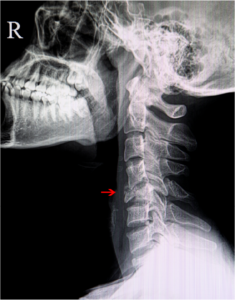

Cervical Fracture

The neck is made up of seven tiny bones called cervical vertebrae (C1-C7). These are protected by spongy vertebral disks present between them and supported…